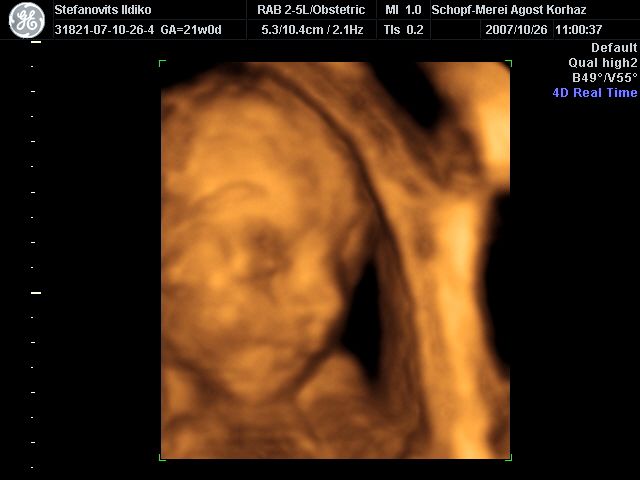

4D Ultrahang - 21+1 (07/10/26, Bp.)

4D - 16